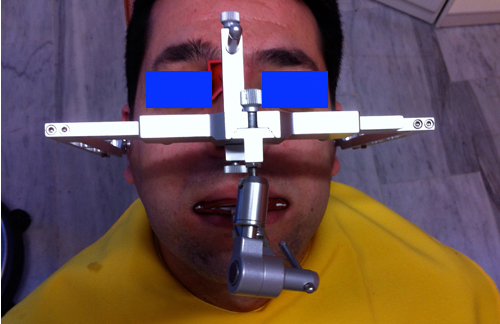

Palabras Clave: ELG: Estereolitográfico OH: Oclusión Habitual ORC: Oclusión en Relación Céntrica Paciente de 35 años de edad ,sexo masculino que lo derivan para implantar el tercer cuadrante. A la auscultación presenta ruidos articulares de tipo chasquido que remiten temporalmente luego de limitación de apertura bucal y maniobras quinesiológicas distractoras. También se observan recidivas de caries en algunos empastes y falta de disclusión canina de ambos lados. Se estudia el caso desde un punto de vista clínico, scanografico mediante Dentascan y tridimensional mediante montaje en articulador. A partir del scanner se obtienen datos para confeccionar modelo estereolitográfico (ELG),operar en el y construir férula quirúrgica dento-muco soportada. Habitualmente se procede directamente a implantar, dado que ese era el requerimiento del profesional derivante y el deseo del enfermo. Sin embargo, esa actitud enmascararía otro tipo de problemas que la boca presenta. Se consulta al odontólogo derivante, y coincide con mi opinión acerca de que si solo se lo implanta, sin corregir la posición mandibular, la situación de las ATMs, los empastes sin anatomía y la falta de disclusiones, el resultado final no será el deseado y su eficacia masticatoria no funcionará optimamente. Consultado el paciente coincide y acepta ese concepto y entonces procedemos a confeccionar un Jig de Lucia a partir del montaje de estudio, y lo dejamos puesto en boca toda la noche anterior a la consulta, para proceder a realizar un ajuste oclusal al día siguiente sin engramas anteriores, lo que facilita no tener que relajar nuevamente con laminillas de Long. En esta etapa pierde el implante correspondiente a la pieza 4.7 que traía en boca. Estabilizado el sistema, procedemos a la parte quirúrgica, comenzando por instalar la férula, retirar opérculos gingivales mediante bisturí circular, fresado óseo e instalación de implantes ,toma de impresión a cubeta fenestrada (pegando con metacrilato sin cambios dimensionales, los transfers a la cubeta especialmente diseñada.(1º método de pasividad protética utilizado), e instalación de tornillos de cicatrización. Inmediatamente de retirada la cubeta de boca y colocadas las réplicas de los implantes, procedemos a ferulizar los “ápices” de las réplicas para que no sufran movimientos durante el llenado de la impresión.(2º método de pasividad protética utilizado). Controlamos radiograficamente Tres meses después, procedemos a tomar nuevos registros de arco facial, registros intermaxilares en Oclusión en Relación céntrica, montaje de los modelos obtenidos intra operatoriamente y confección de un conjunto de cuatro coronas provisionales de metacrilato en el sector implantado y las correspondientes al maxilar superior. Verificada la perfecta función de todos los componentes, ausencia de todo tipo de síntoma y comprobada la paz en todo el sistema, procedemos tiempo después a confeccionar las fundas definitivas, que constituyen el “cerrojo” de la dinámica del mismo. Por último, corroboramos la oclusión fundamentalmente en lo que hace a la: